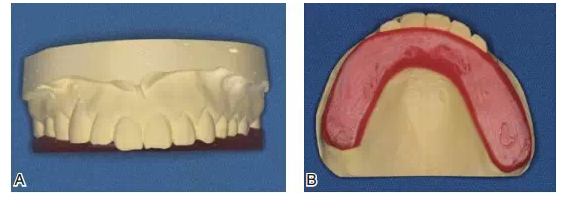

圖10該患者咬合重建修復(fù)前的關(guān)鍵是先確定牙合平面。A制作馬蹄型蠟板壓在上頜咬合面;B調(diào)整蠟板厚度和方向,用牙合平面板確定上頜牙合平面,牙合平面在前牙區(qū)和瞳孔連線平行,在后牙區(qū)和鼻翼耳屏面平行

圖11蠟板所代表的牙合平面

圖12在蠟板下方放置一個石膏平臺